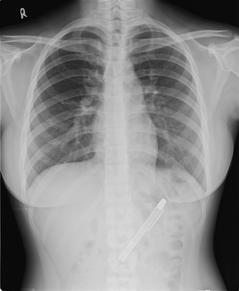

从X光片,可看到这支钢笔卡在胃中。来源:台湾《联合报》

中新网6月30日电 据台湾《联合报》报道,台湾一名患有忧郁症的20岁少女,半年来久咳不愈,胃部疼痛,向医生求助,医生为她照X光,发现胃部竟有一支约10公分长的笔,花了约一个小时,用内视镜异物夹将笔夹出,笔身都已生锈。